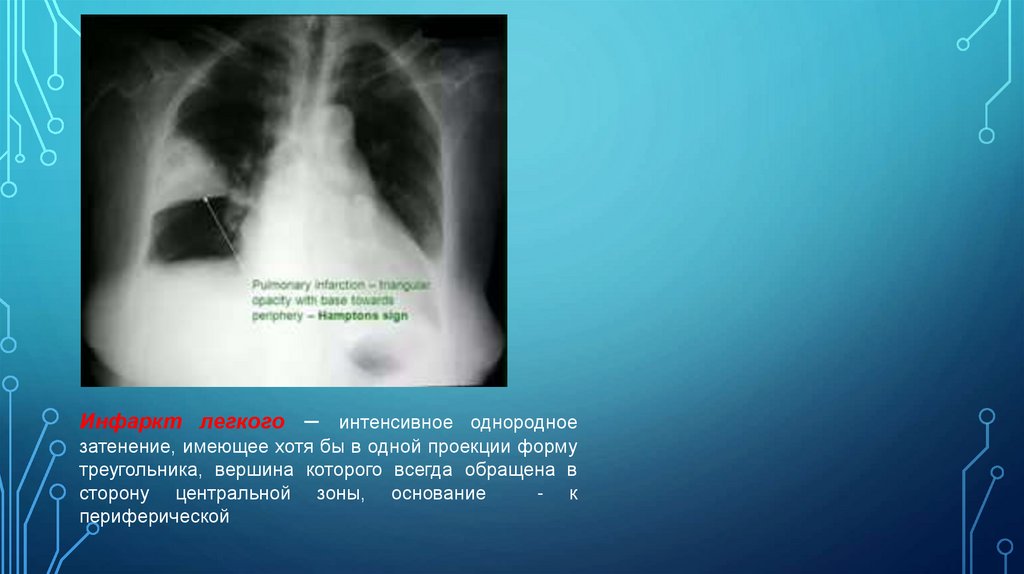

Д) Инфаркт легкого – интенсивное однородное затенение, имеющее хотя бы в

одной проекции форму треугольника, вершина которого всегда обращена в сторону

центральной зоны, основание - к периферической

Инфаркт легкого – интенсивное однородное

затенение, имеющее хотя бы в одной проекции форму

треугольника, вершина которого всегда обращена в

сторону центральной зоны, основание

- к

периферической